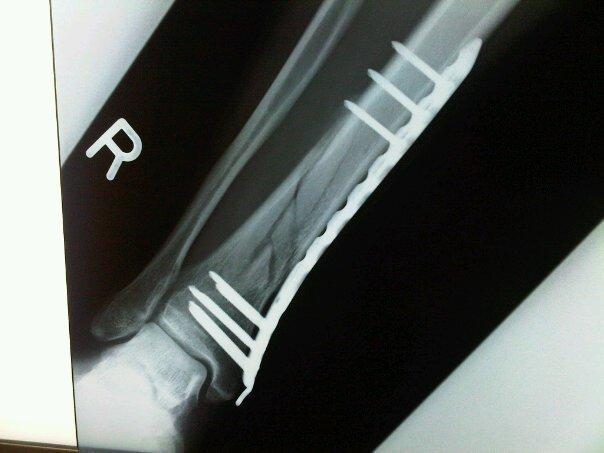

↑

脛骨下端 骨折線が徐々に薄くなりつつあります。

近位部3本の一番下あたりの骨が成長してます。